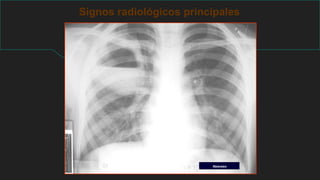

Signos radiológicos principales

Enfermedad pulmonar difusa

PATRONES

RADIOLÓGICOS

LINEAL

RETICULAR

NODULAR

RETICULONODULAR